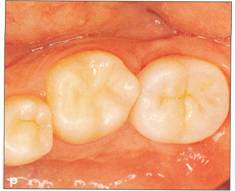

Fi 545e45f g 5-31 Fi 545e45f ve months after transplantation. Fi 545e45f g 5-3m Nine months after transplantation. The calcium hydroxide has been replaced with gutta percha. |

Fi 545e45f g 5-3n The donor tooth before restoration with a ceramic crown. Fi 545e45f g 5-30 The ceramic crown. |